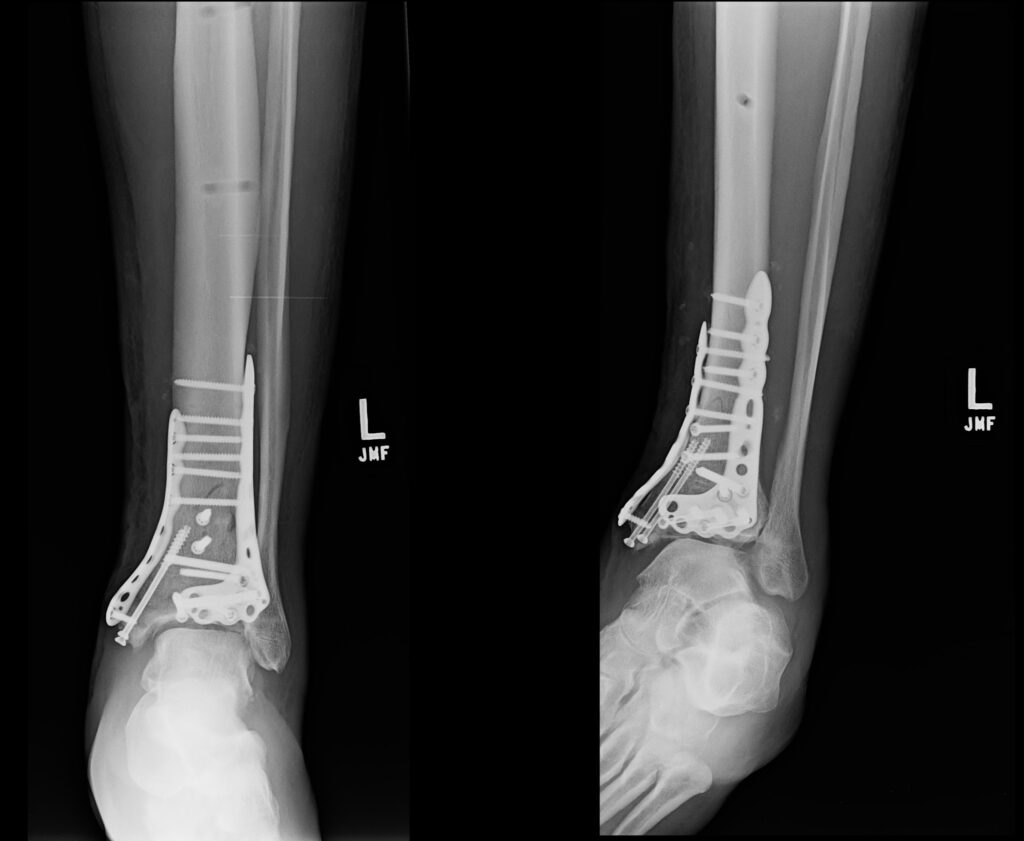

Three surgeries and four months later, Neal was able to start bearing weight again on his leg and begin physical therapy. The muscles in his leg had pretty much turned to jelly by then, so the road to gaining strength and mobility was going to take many months. He could start sitting on a bike again and spin the pedals, but there was no way he could do that safely outside without the real risk of falling over.